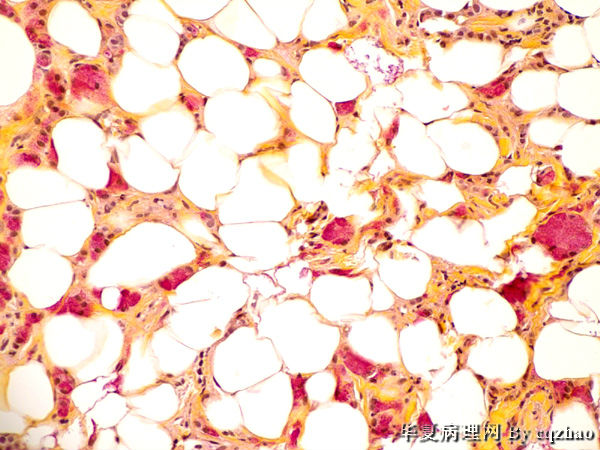

Breast core biopsy

• 63y/f with imaging finding of R breast asymmetry (cqz B-44)图1

Fig 1 10x Fig 2 20x, fig 3 40x

Fig 4 another area 20x

Fig 5 40x  same area as fig 4

It is invasive ductal carcinoma with apocrine feature and also cytoplasmic mucin production.

It is a rare case. Bottomly it is invasive ductal carcinoma.

Singet ring ductal carcinoma??

伴有大汗腺化生的浸润性导管癌。

镜下瘤细胞胞体较小,核圆形或印戒样,胞浆嗜碱性,形成条索状、小巢状,在胶原纤维内穿插走行,周围脂肪组织内亦见瘤组织浸润。P120,E-CD标记?

The patient has no any history of cancers. ER and PR (not shown) are strongly and diffusely positive.

Metastatic tumor is excluded basically. It is a breast carcinoma.

What type?